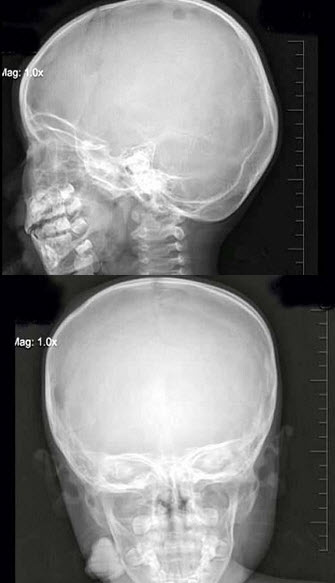

130、单项选择题

3岁,男,发热伴头顶部局限性疼痛1周,右额顶部可见局限性骨缺损,最可能的诊断是()

A.蛛网膜颗粒压迹

B.先天性颅骨缺损

C.嗜酸性肉芽肿

D.局限性骨皮质缺损

E.以上均不是